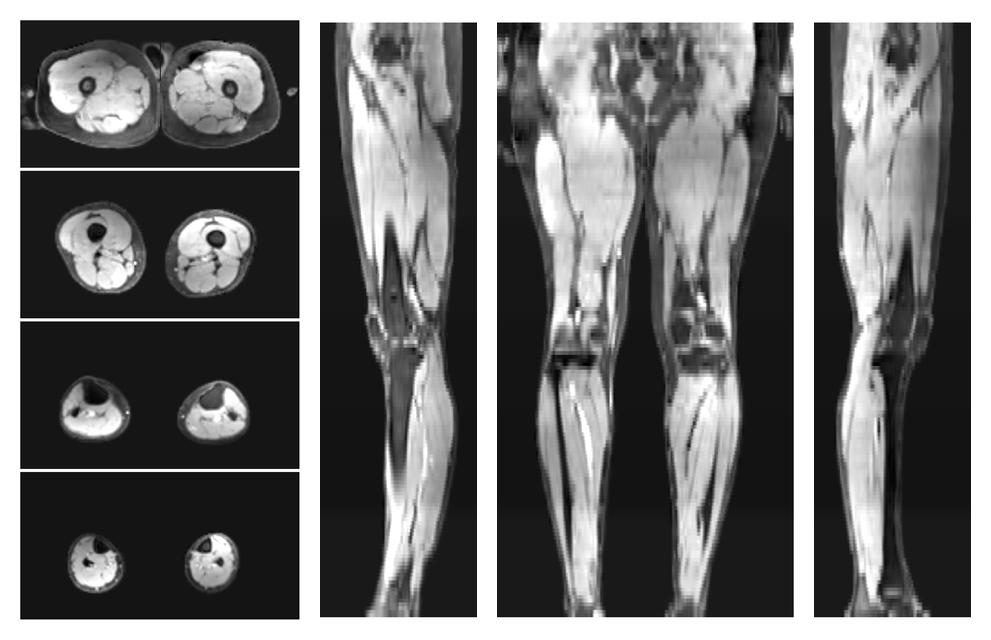

• Out phase image

The out-phase image of the dixon reconstruction for water fat quantification.